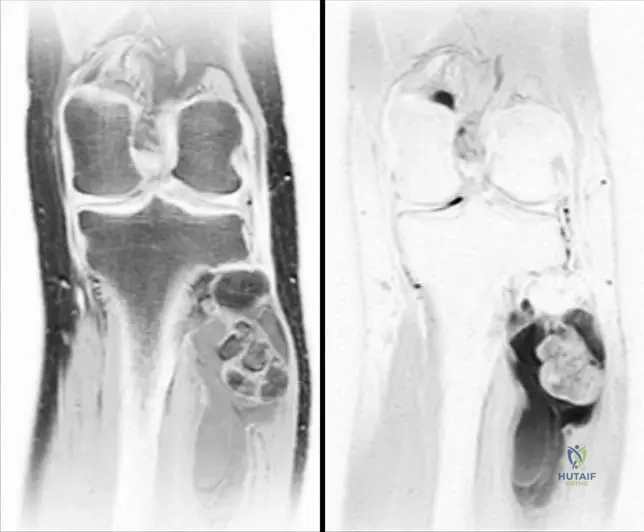

Correct Answer: A

Rationale: The clinical context for Fig. 9.17 states: "Proton density (a), T2 (b), images of the lesion. Note the heterogeneity and intimate association with the fibula." Main Distractor: B) Tibia. While the tibia is in the lower leg, the text specifically mentions the "intimate association with the fibula" for this particular image.

Rationale: The clinical context for Fig. 9.18 explicitly states: "Resected proximal fibula with adjacent liposarcoma." Main Distractor: B) Malignant fibrous histiocytoma (MFH). While MFH is a type of soft tissue sarcoma mentioned in the general text, the specific image context identifies the tumor as a liposarcoma.